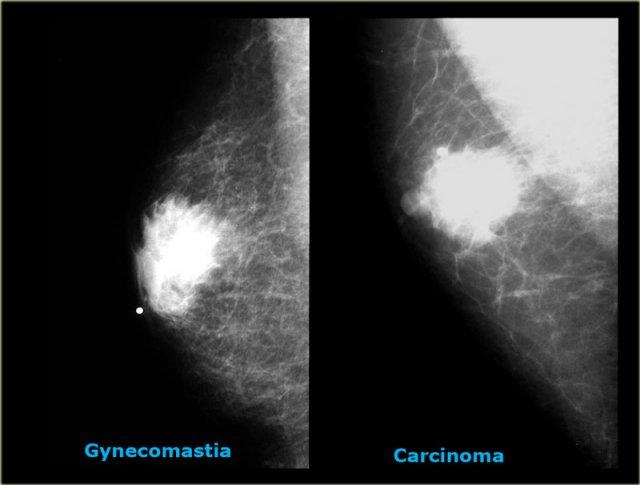

Bên trái là thêm hai trường hợp nữa.

Ở ngoài cùng bên trái là hình ảnh vú nam to lan tỏa.

Bên phải là một khối ung thư lớn có bờ được bao bọc.

Các trường hợp cuối cùng ở bên trái trông rất giống nhau.

Dựa trên nhũ ảnh, không thể phân biệt được hai trường hợp này.

Trong những tình huống hiếm gặp như vậy, cần phải tiến hành sinh thiết.